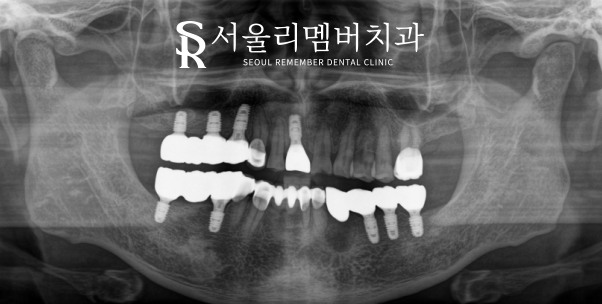

앞서 계획했던 대로 모든 과정을 마무리했습니다.

수면 임플란트 식립을 진행하여

어금니 수술을 도와드렸는데요.

상악동의 막이 아래로 내려와 있어

거상술 및 골이식까지 동반했습니다.

이때 그대로 심어버리게 되면

픽스쳐가 제대로 고정되지 않거나

수술 실패로 이어질 수 있기 때문에

꼼꼼히 확인하여 진료를 하는 것이 중요합니다.

서울대입구치과 몇 달간의 과정이 마무리되고

모든 식립을 마칠 수 있었는데요.

텅 비어 있던 어금니가 픽스처 및 크라운으로

꽉 채워져 있는 것을 볼 수 있습니다.

훨씬 심미적이고 건강한 모습인데요.